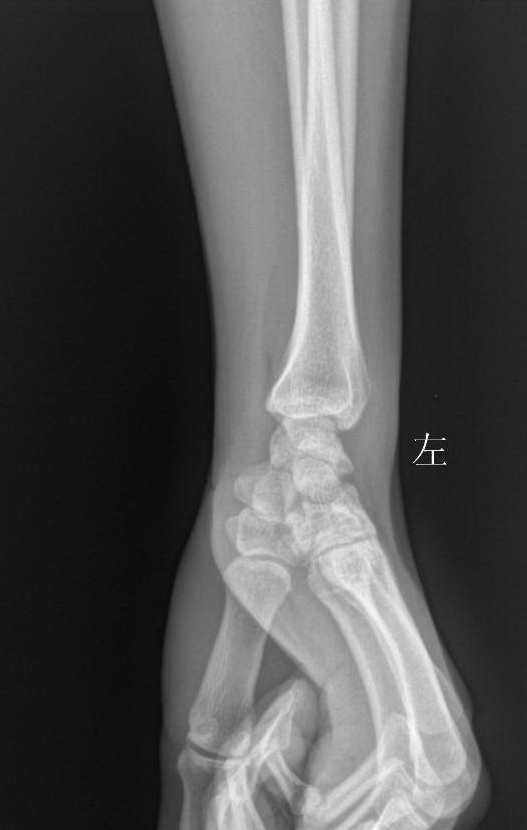

标题: X7319:F 50岁,左腕肿痛数年 [打印本页]

标题: X7319:F 50岁,左腕肿痛数年

大多角骨无菌性坏死可能。

大多角骨密度增高,尺骨过长,应该考虑到尺骨撞击综合征

大多角骨密度增高,尺骨过长,应该考虑到尺骨撞击综合征,完善病史。

我怎么看都感觉多角骨有问题,怎么大家都认为“未见异常”呢?难道是《皇帝的新衣》吗?哈哈哈哈哈!

考虑多角骨无菌性坏死可能。具体是大还是小多角骨,判断不了。